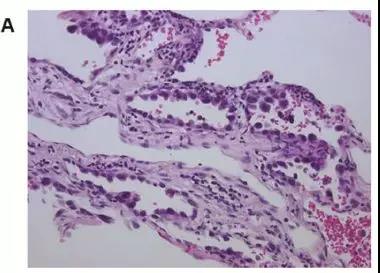

图A,病理检查肿瘤周边没有STAS